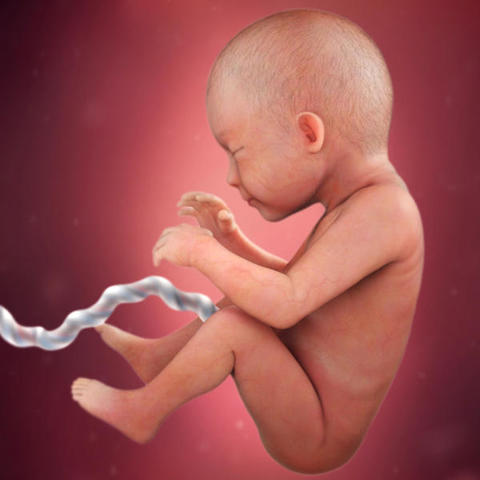

Mide entre 17 y 22 milímetros. Y físicamente también ha cambiado mucho: la cola ha desaparecido y la cabeza se ha separado un poco del cuerpo gracias a un incipiente cuello que humaniza su silueta.

Al bebé que está creciendo dentro del útero materno aún le queda mucho por crecer. En apenas siete semanas -ni dos meses- ha pasado de los 2 milímetros a los 8,5 centímetros que mide ahora desde la cabeza a los talones.

El bebé mide alrededor de 20 centímetros y pesa unos 600 gramos.

El bebé pesa ya alrededor de kilo y medio y mide unos 43 centímetros. A partir de esta semana el lanugo, el fino vello que cubre su cuerpo, empieza a caerse muy lentamente.

El bebé mide alrededor de 42 centímetros y pesa unos 2 kilos.

Ahora el bebé pesa alrededor de 3 o 3,5 kilos y su longitud oscila entre los 49 y los 53 centímetros. Tiene unas uñas muy largas.